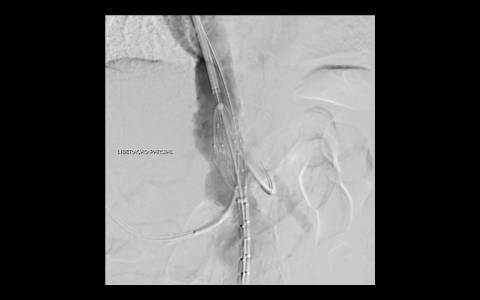

A avaliação por tomografia computadorizada evidenciou um aneurisma infra-renal de colo hostil e acessos vasculares com muita ateromatose. Diante do contexto clínico e de imagem foi optado pelo tratamento endovascular com endoprótese de baixo perfil Incraft CORDIS e técnica de Snorkel Grafts com stents Palmaz CORDIS para as artérias renais.